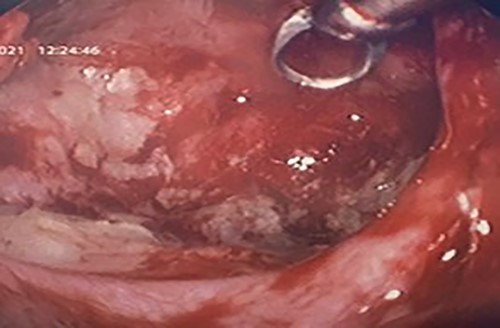

Flexible nasendoscopy offered little in terms of diagnostic benefit. An exam under anesthetic with a view to removing the ectopic tooth via endoscopic sinus surgery was warranted. Right middle turbinate trimming along with a right maxillary antrostomy was performed. The tooth was immediately identified at the antrum as depicted in Figs 4–6. The bony capsule of the tooth was entered and, on manipulation, a second ectopic tooth was identified (Fig. 7) both of which were removed en bloc. The cystic component within the maxillary sinus was marsupilized and extracted. The sinus cavity can be viewed with the utilization of 70° endoscope (Fig. 8). This facilitated bipolar cautery of the base of the cyst and confirmed the absence of an oroantral fistula.

Intra-operative image of the ectopic tooth at the right osteomeatal complex.

Intra-operative image of the ectopic tooth at the right osteomeatal complex, with curved suction facilitating enucleation.